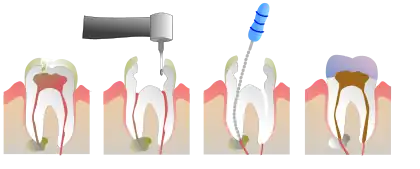

Root canal is also a colloquial term for a dental operation, endodontic therapy, wherein the pulp is cleaned out, the space disinfected and then filled.

When rotary nickel titanium (NiTi) files are used in canals with flat-oval or tear-shaped cross sections, a circular bore is created due to the rotational action of the metal. Also, small cavities within the canal such as the buccal or lingual recesses may not be instrumented within the tooth, potentially leaving residual disease during disinfection.

Tissue or biofilm remnants along such un-instrumented recesses may lead to failure due to both inadequate disinfection and the inability to properly obturate the root-canal space. Consequently, the biofilm should be removed with a disinfectant, commonly sodium hypochlorite, during root canal treatment.